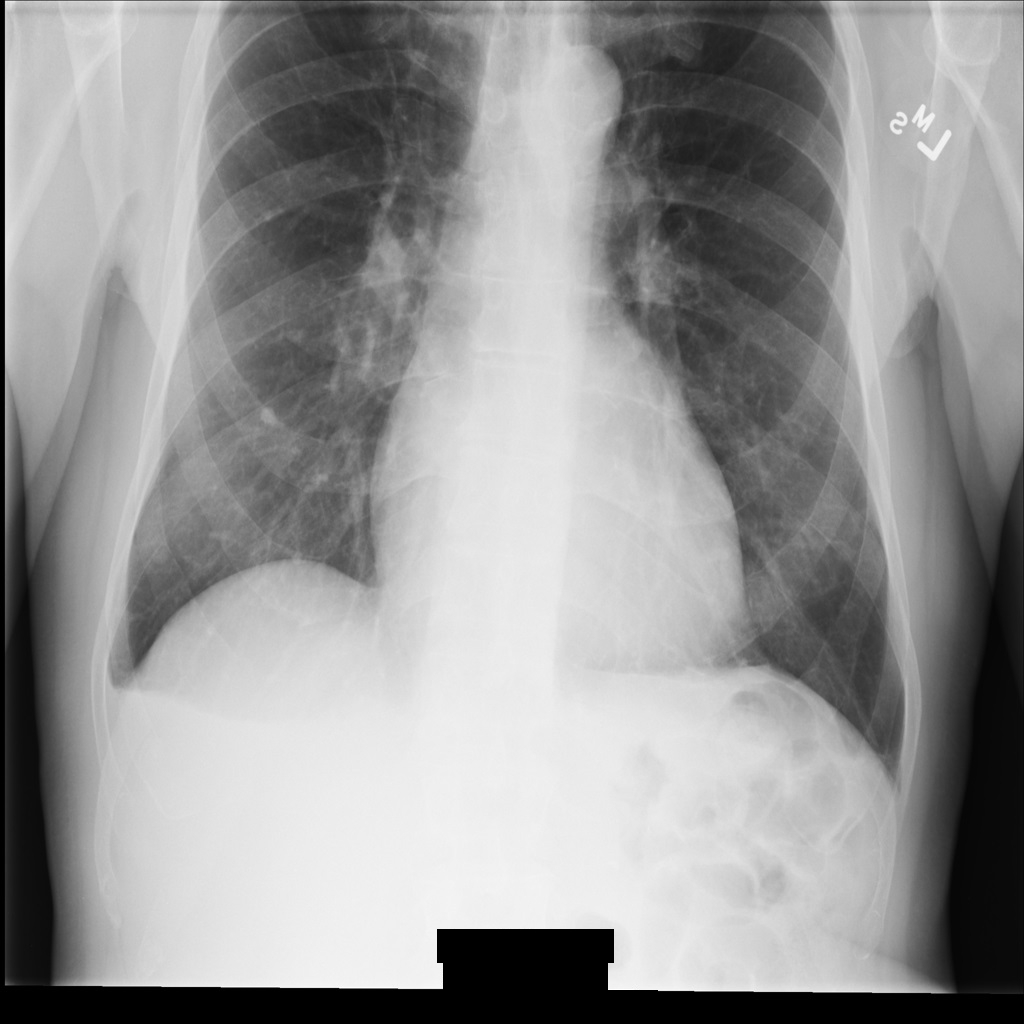

After de-identifying the image using REDACT_SENSITIVE_TEXT_CLEAN_DESCRIPTORS, the image

looks like this. Notice that not all the burned-in text at the bottom of the

image has been redacted. The text Female is still shown, because

PatientSex (0010,0040) isn't one of the default DICOM infoTypes.